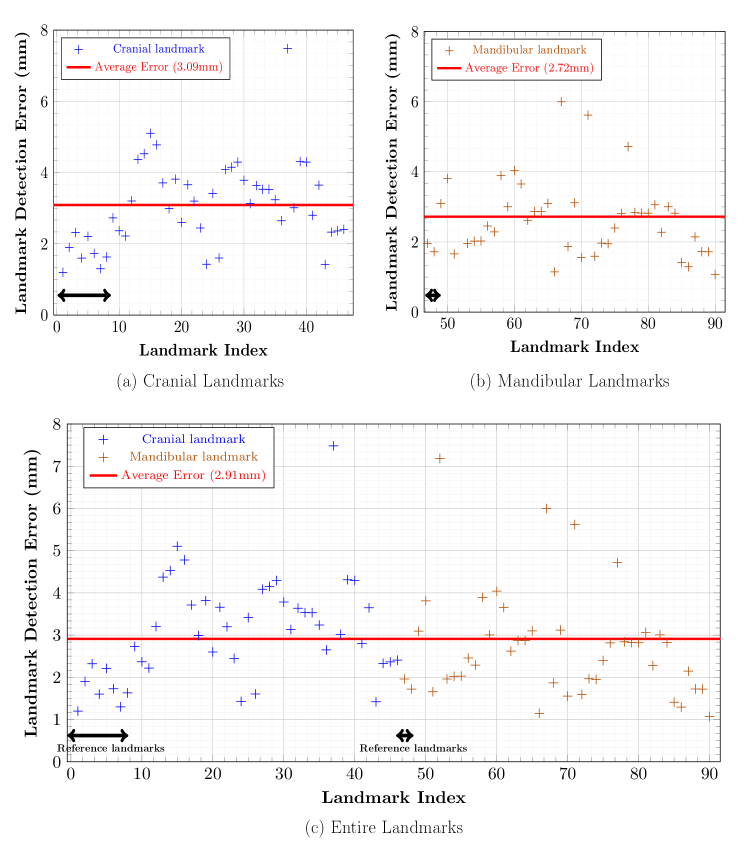

Figures 7(b) and 8(b) show the qualitative and quantitative results of the 3D CNNs. The mean 3D distance error decreased to 2.72 mm when compared to the initial detection error of 4.23 mm (Figure 6(b)). According to results shown in Table 3, the proposed method achieved an error range of 1 to 4 mm for the detection of most landmarks. In addition, as shown in Figure 10(b), the proposed method significantly reduced the mean and variance of error for the test subjects, compared to the initial detection.

Figures 7(a) and 8(a) show the final cranial landmark estimation results in qualitative and quantitative formats. The mean detection error for all cranial landmarks was 3.09 mm, which decreased from the initial estimation error of 3.68 mm (Figure 6(a)). As shown in Table 3, the error for most cranial landmarks fell within the range of 1 to 4 mm.

The proposed method employed coarse-to-fine detection, where appropriate strategies for mandibular and cranial landmarks were considered for their different properties. The experiments confirmed the good performance of the proposed method, even when the size of the training dataset is limited. As the amount of training data increases, we expect the detection accuracy to be further improved.